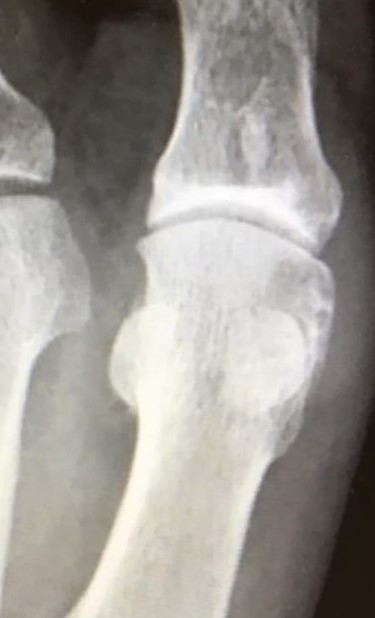

(A + B): (A) Anteroposterior, weight-bearing, X-ray view of the left foot. The red arrow shows a lytic lesion of the subchondral bone, indicating a possible OD lesion on the MH. The black arrow shows the formation of a small, lateral osteophyte. (B) Oblique X-ray view of the left foot. The red arrow shows again radiolucency of the cortical bone as well as small fragmentation of the MH.

Standing anteroposterior (AP), oblique and lateral radiographs of the affected foot were taken. On the AP and oblique views, an OD lesion of the 1st MH was visible (lytic lesion of the subchondral bone and subchondral sclerosis formation) with a lateral-forming osteophyte (Fig. 1A and B). Magnetic resonance imaging (MRI) of the left foot clearly shows the osteochondral defect of the 1st MH (Figs 2 and 3).